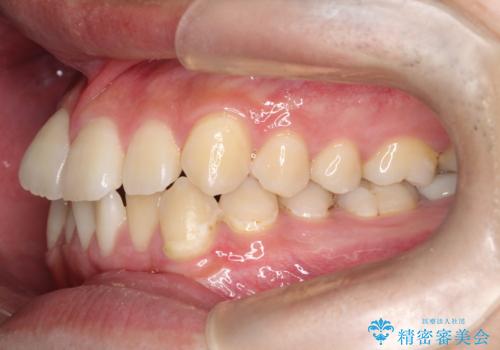

【ワイヤー矯正】前歯の凸凹を治したい。

- 前歯の凸凹を主訴に来院されました。

患者様がマウスピース矯正の使用時間に不安があるため、ワイヤー矯正にて治療を行なっております。